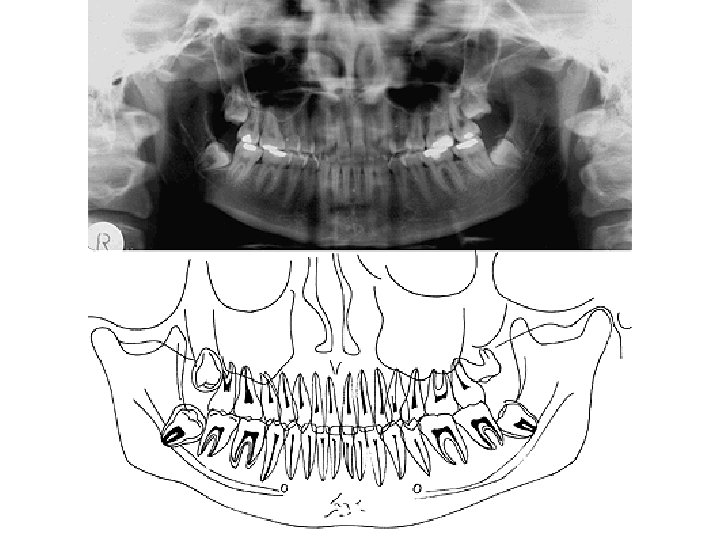

DENTES INCISIVI - 2 DENS CANINUS – 1 DENTES MOLARES - 2 DENTES DECIDUI

Eruption: I 6 th- 8 th month II 8 th-12 th month III 16 th-20 th month IV 12 th-16 th month V 20 th-36 th month I, IV, III, V Exchange of the teeth: 1 2 3 4 5 6 7 8 7 th-8 th year 8 th-9 th year 11 th-13 th year 9 th-11 th year 11 th-13 th year 6 th-7 th year 12 th-14 th year 17 th-40 th year 6, 1, 2, 4, 3, 5, 7, 8